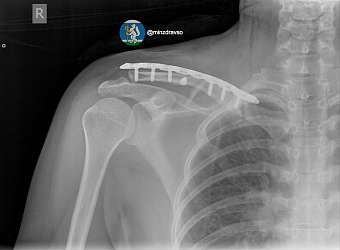

- Долой костыли! В «Липовке» за четыре дня вернули радость движения режевлянке со сложным переломом

- В Артёмовской ЦРБ проведено более двух десятков операций по «детскому» остеосинтезу